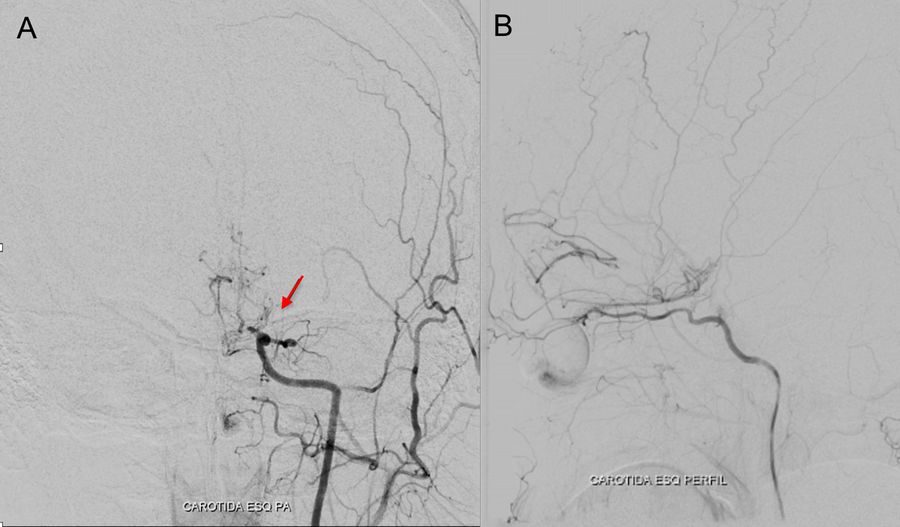

Catheter angiography was performed with the following findings:

• Occlusion at the proximal third of the cervical segment of the right internal carotid artery

• Stenosis of the supraclinoid segment of the left internal carotid artery

• Proximal stenosis of the anterior and middle cerebral arteries with collateral «smoke puff» vessels, which are characteristic findings of moyamoya disease

• Collateral circulation from the internal maxillary artery to the ipsilateral carotid territory

• Collateral irrigation of the carotid territory from the posterior circulation through a patent posterior communicating artery

A DSA (digital subtraction angiography) was performed pre-operatively to assess the occlusions of the internal and external

carotid arteries, as well as stenosis of the arteries and the feeding and draining blood vessels of the arteriovenous malformation, as

shown in the images below.